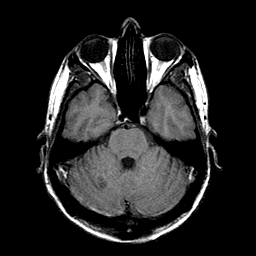

Sarcoma, MR Study #1 mr-t1 -- Slice #6

[Home][Help][Clinical] Slice 6